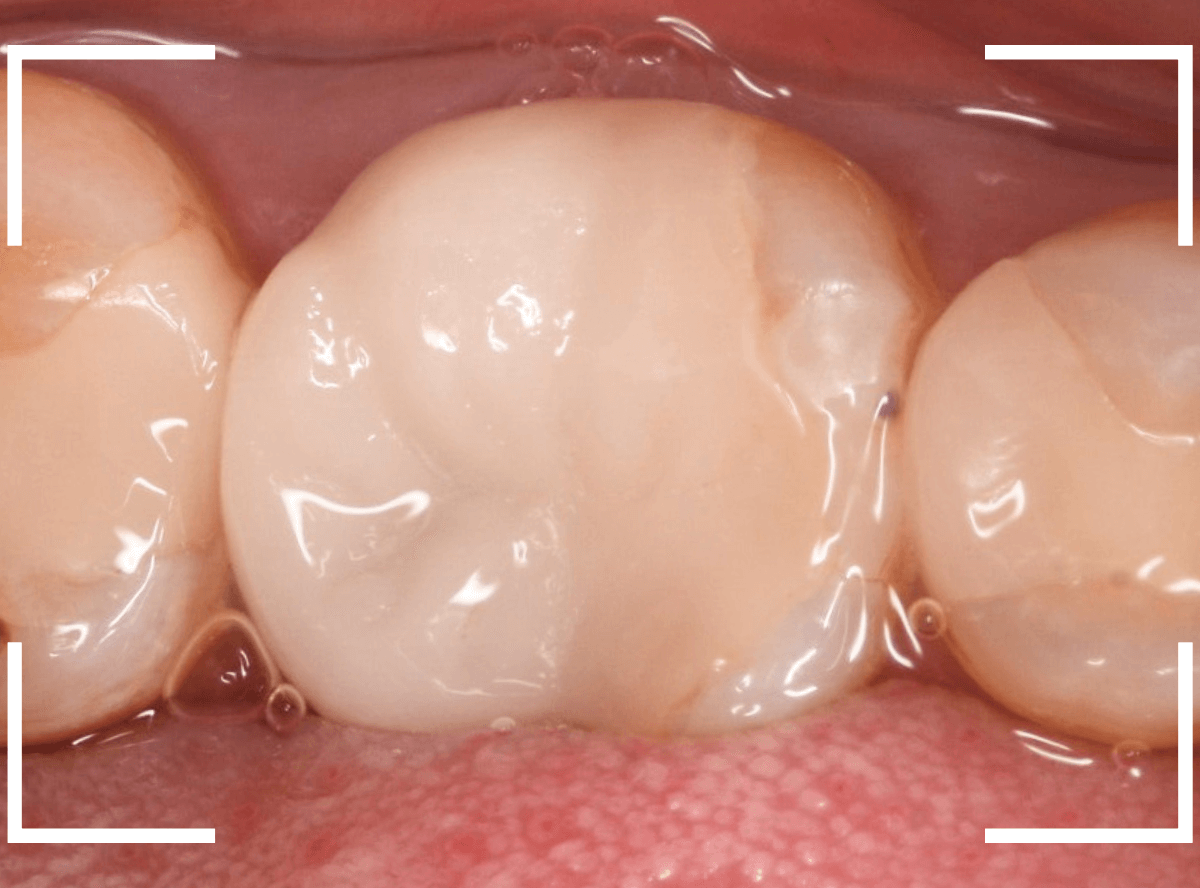

お口の中にsetしたところです。

周りの歯と自然に合わせられたかと思います。

お口の中全体でみたところです。

全体で見ても、違和感少なく仕上げられたかと思います。